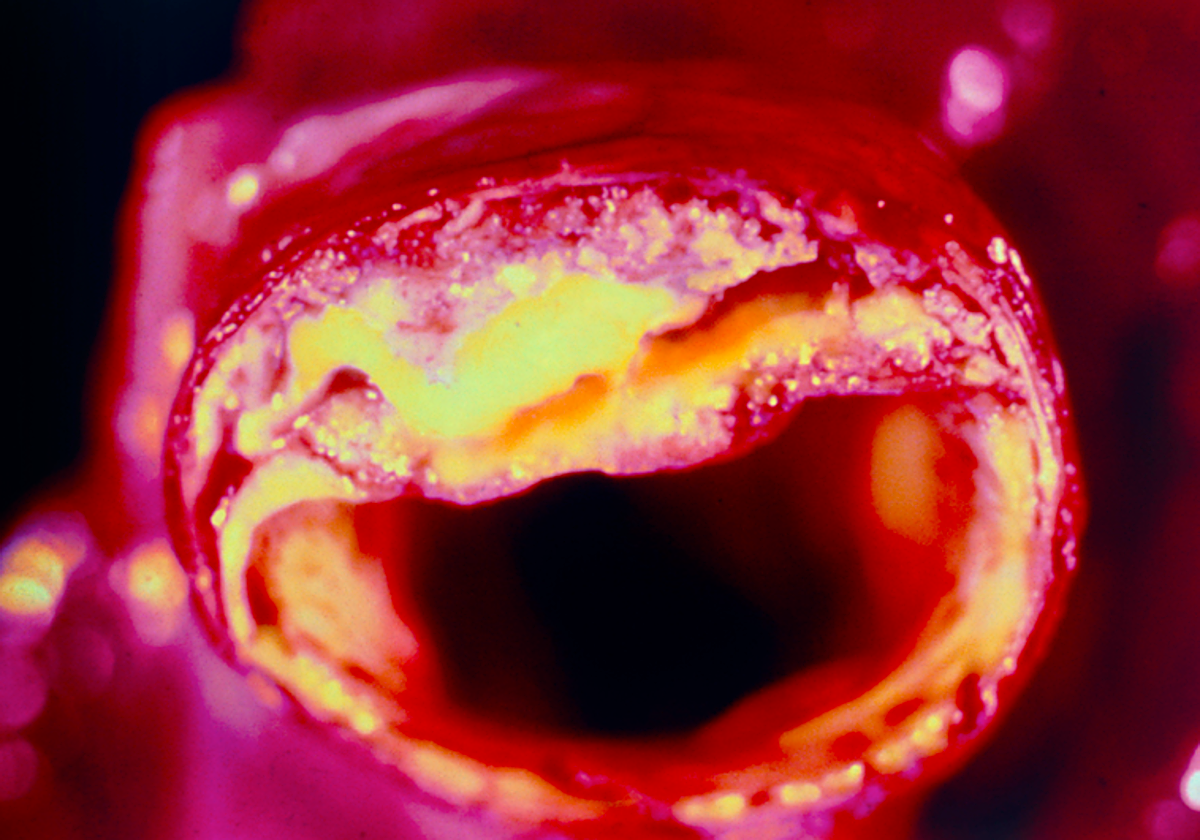

La Lp (a) se genera en el hígado y tiene similitudes con el LDL, también conocido como lipoproteína de baja densidad o «colesterol malo». A diferencia de otros tipos de partículas de colesterol, los niveles de Lp(a) están determinados genéticamente en un 80-90%. La estructura de la partícula de Lp(a) es responsable de la placa en las arterias, lo que aumenta considerablemente el riesgo de ataques cardíacos y accidentes cerebrovasculares.

La Lp(a) es un factor de riesgo independiente para las enfermedades cardiovasculares. El nivel de Lp(a) que se encuentra en la sangre de una persona está determinado genéticamente. Esto significa que a diferencia de otros factores de riesgo cardíacos, la Lp(a) no se puede modificar por la dieta o el ejercicio. Su nivel de Lp(a) es el mismo a los 5 años que a los 45 años.